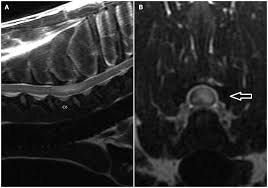

У кошек с предполагаемым острым инфарктом описаны очаги T1 iso/гипоинтенсивные и T2 гиперинтенсивные, иногда с мягким контраст‑усилением; при отсутствии другой системной патологии FCE рассматривается как вероятная этиология.

Для собак детально описаны МР‑находки у пациентов с предполагаемыми инфарктами/ишемической миелопатией и FCEM.

Важно: “нормальная МРТ” не исключает FCEM в первые сутки

Классическое клиническое знание, отражённое в обзорах, — МР‑изменения при FCE/FCEM могут быть минимальными или неочевидными в самые ранние сроки, что и объясняет интерес к DWI.